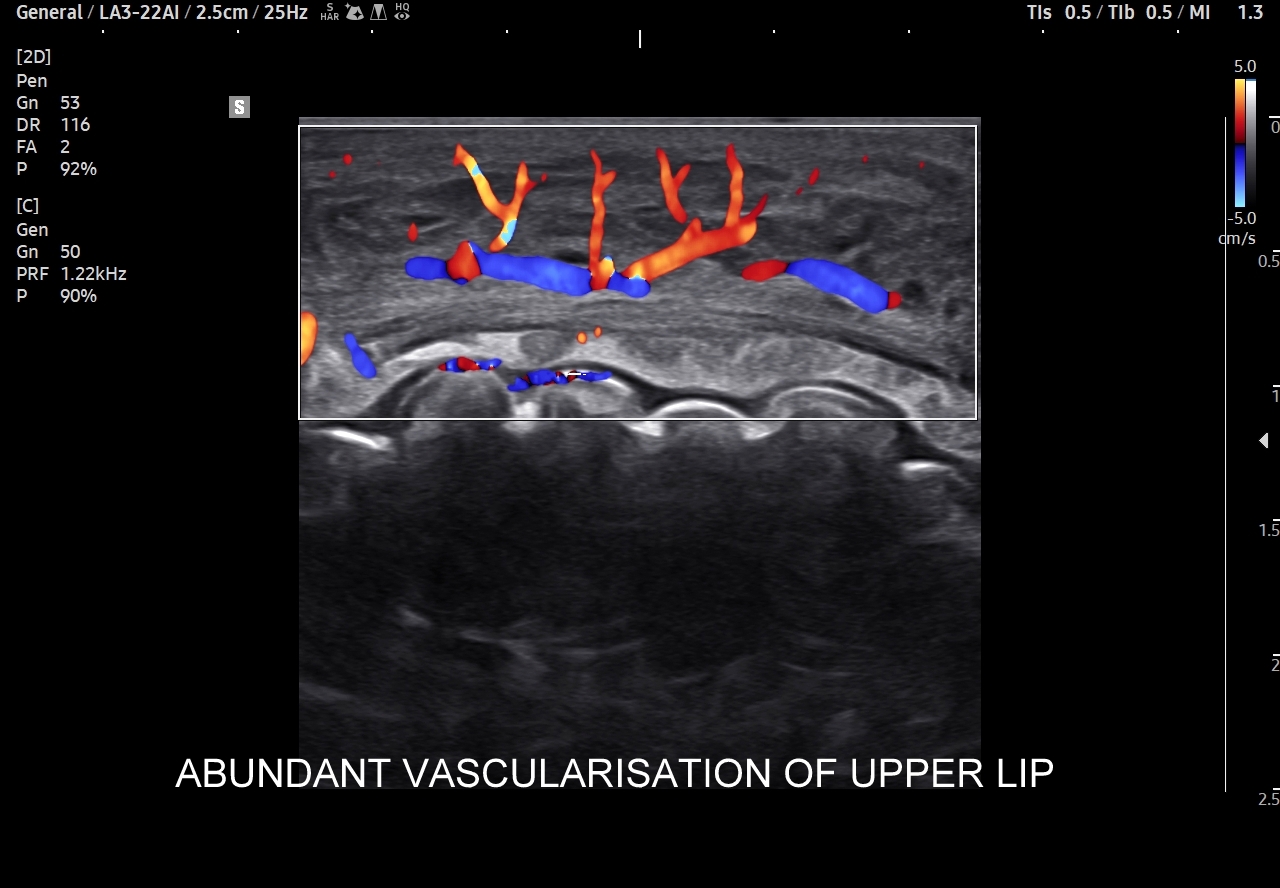

Trójkąt śmierci na twarzy obejmuje również usta. Należy pamiętać, iż są one organami mocno unaczynionymi, co przedstawione jest na załączonych obrazach sonograficznych, a wszelkie infekcje ostre bądź przewlekłe, spontaniczne lub jatrogenne również mogą być przyczyną w/w infekcyjnych powikłań wstępujących oraz zstępujących.